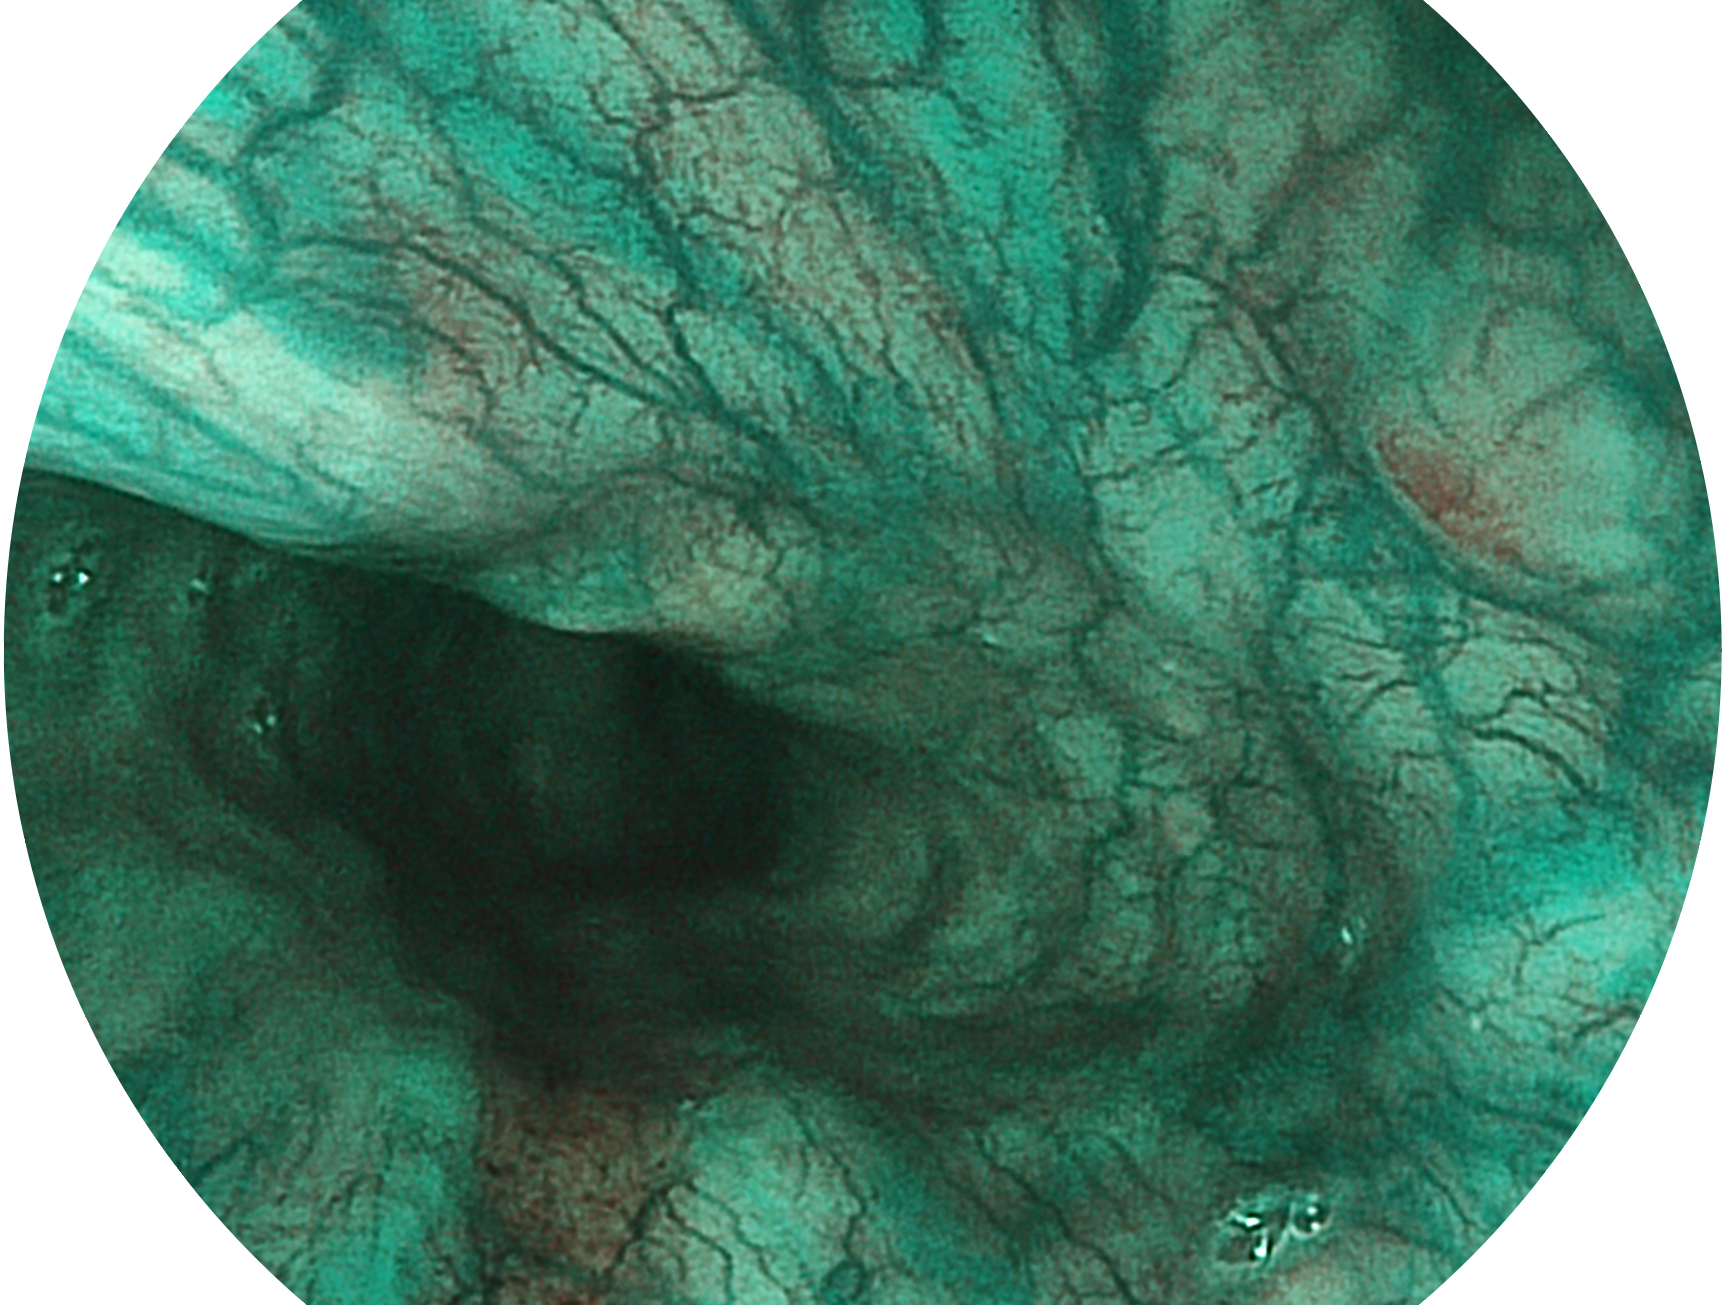

环球UG官网新开发的内镜染色技术,主要是基于多波长LED 光源的开发,VLS-55Q 四波长LED 光源是由四个不同颜色的LED光按照相应照明模式所规定的特定发光比例进行合束后形成,合束后形成的照明光的光谱由红光、绿光、蓝光及蓝紫光这四个不同的波段范围构成。具有更高光谱自由度,通过光谱比例的控制,实现了聚谱成像技术,英文全称为“Spectral Focused Imaging, SFI”,缩写为“SFI”和光电复合染色成像技术,英文全称为“Versatile Intelligent Staining Technology, VIST”,缩写为“VIST”。